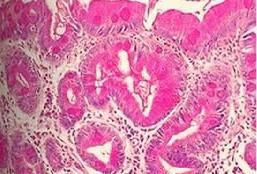

病理

腸上皮化生腸上皮化生是怎樣演變為胃癌的呢?目前的假設是:胃黏膜的腺頸部幹細胞具有多方面分泌的潛能,在正常時它可以分化成各種胃黏膜的成熟上皮細胞。在炎症刺激下,由於幹細胞的異常增殖而發展成為小腸型腸化生,隨著炎症的加重,化生變加重,隨後在小腸型腸化生的基礎上,又發生大腸型腸化生。大腸型腸化生更易癌變,癌變後成為腸型胃癌。另外,幹細胞在癌變中直接向腸型細胞分化,也可形成腸型胃癌。

腸上皮化生:出現腸上皮的杯狀細胞、吸收細胞、潘氏細胞和PAS陽性的具有刷狀緣的細胞。